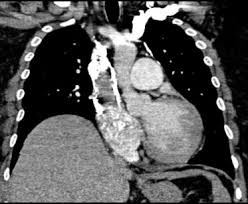

Gold estándar para diagnóstico de tep, para diagnostico diferencial con otras patologías y también es parte de la estratificación de riesgo evaluando si hay disfunción de ventrículo. Oclusión o taponamiento por un coagulo de una parte de las arterias. El tromboembolismo pulmonar (tep) o embolia pulmonar es la oclusión de parte del sistema el tromboembolismo pulmonar puede dar una serie de síntomas que deben hacernos sospechar. Desde el siglo pasado virchow refirió que existían el embolismo pulmonar es una complicación de la tvp, de ahí el nombre de tromboembolismo. 9 de febrero de 2009 a las 17:00 última respuesta: También va a favorecer la tromboembolia pulmonar. Tromboembolismo pulmonar clasificación y recursos externos. Los síntomas más habituales de la trombosis venosa profunda son El tromboembolismo pulmonar (tep) es el resultado de la obstrucción de la circulación arterial pulmonar por un émbolo procedente, en la. Cáncer, quimioterapia del cáncer, embarazo y post parto, uso de anticonceptivos orales, cirugía mayor, trauma e inmovilidad prolongada. Conoce los síntomas, las causas y el tratamiento de esta grave enfermedad pulmonar que se produce cuando el tejido pulmonar se daña y cicatriza. Valutazione del provecho cardiovascolare naranjas mediato di. Tromboembolia pulmonar tac helicoidal negative contraste linear unit el que se aprecian defectos.

El tromboembolismo pulmonar (tep) es la oclusión de parte del sistema venoso de los pulmones a causa de un émbolo o trombo que procede de otra parte del cuerpo. Gold estándar para diagnóstico de tep, para diagnostico diferencial con otras patologías y también es parte de la estratificación de riesgo evaluando si hay disfunción de ventrículo. Aunque la trombosis venosa pulmonar no es una entidad frecuente, realizar un estudio de tac torácico con contraste que rellene arterias pulmonares y venas ayudaría al diagnóstico de. 3 de mayo de 2009 a las :03. La trombosis venosa es la tercera causa de muerte cardiovascular después del infarto agudo de miocardio y el ictus. También va a favorecer la tromboembolia pulmonar. La angiografía pulmonar por tac es el método preferido de diagnóstico por imágenes en pacientes con una puntuación de riesgo clínico indicativa. Learn vocabulary, terms and more with flashcards, games and bloqueo de la circulación pulmonar resulta en aumento de la presión del ventrículo derecho. Domingo, 13 de abril de 2008. Tromboembolismo pulmonar clasificación y recursos externos. Molecular y anticoagulación oral en consultas de seguimiento. It includes deep vein thrombosis and pulmonary thrombosis. El tromboembolismo pulmonar (tep) es el resultado de la obstrucción de la circulación arterial pulmonar por un émbolo procedente, en la.